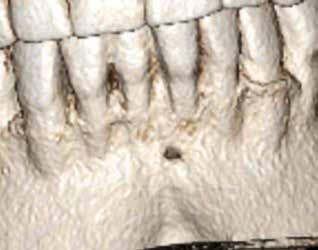

3. a–d ábra: A koronális síkú metszeten jól megfigyelhető a lézió mesio-distalis kiterjedése (a), a szaggitális síkú metszet a lézió vesztibulo-orális nagyságát mutatja (b), a gyökércsúcs körül elhelyezkedő lézió a 3 dimenziós rekonstrukciós képen és a mesio-disztális irányú metszeten is jól megfigyelhető (c–d).

A radiológiai felvételek elemzése során a fog gyökércsúcsának megfelelően radiolucens elváltozást észleltünk, valamint a fognyak területének megfelelően szintén egy radiolucens területet figyelhettünk meg (1–2. ábra). Az elváltozások kiterjedésének és mélységének pontosabb meghatározása érdekében CBCT-felvétel készült (3. ábra). A felvétel alapján Heithersay-féle III. osztályú külső fognyaki gyökérfelszívódást diagnosztizáltunk (Heithersay Class III external cervical invasive root resorption; ECIR). Ezzel egyidejűleg pedig szimptomatikus periapikális periodontitis is fennállt. Ezt követően a pácienst a vizsgálati eredményekről, a kezelési alternatívákról és a várható prognózisról is tájékoztattuk.

A cikkekben bemutatott esetnél a kezelésre szoruló fog gyökércsúcsánál periapikális lézió volt megfigyelhető és ezzel egyidejűleg külső fognyaki gyökérrezorpció is fennállt. A periapikális és a rezorptív lézió méretének pontos meghatározását és térbeli elhelyezkedésének vizsgálatát CBCT-felvétel segítségével végeztük.